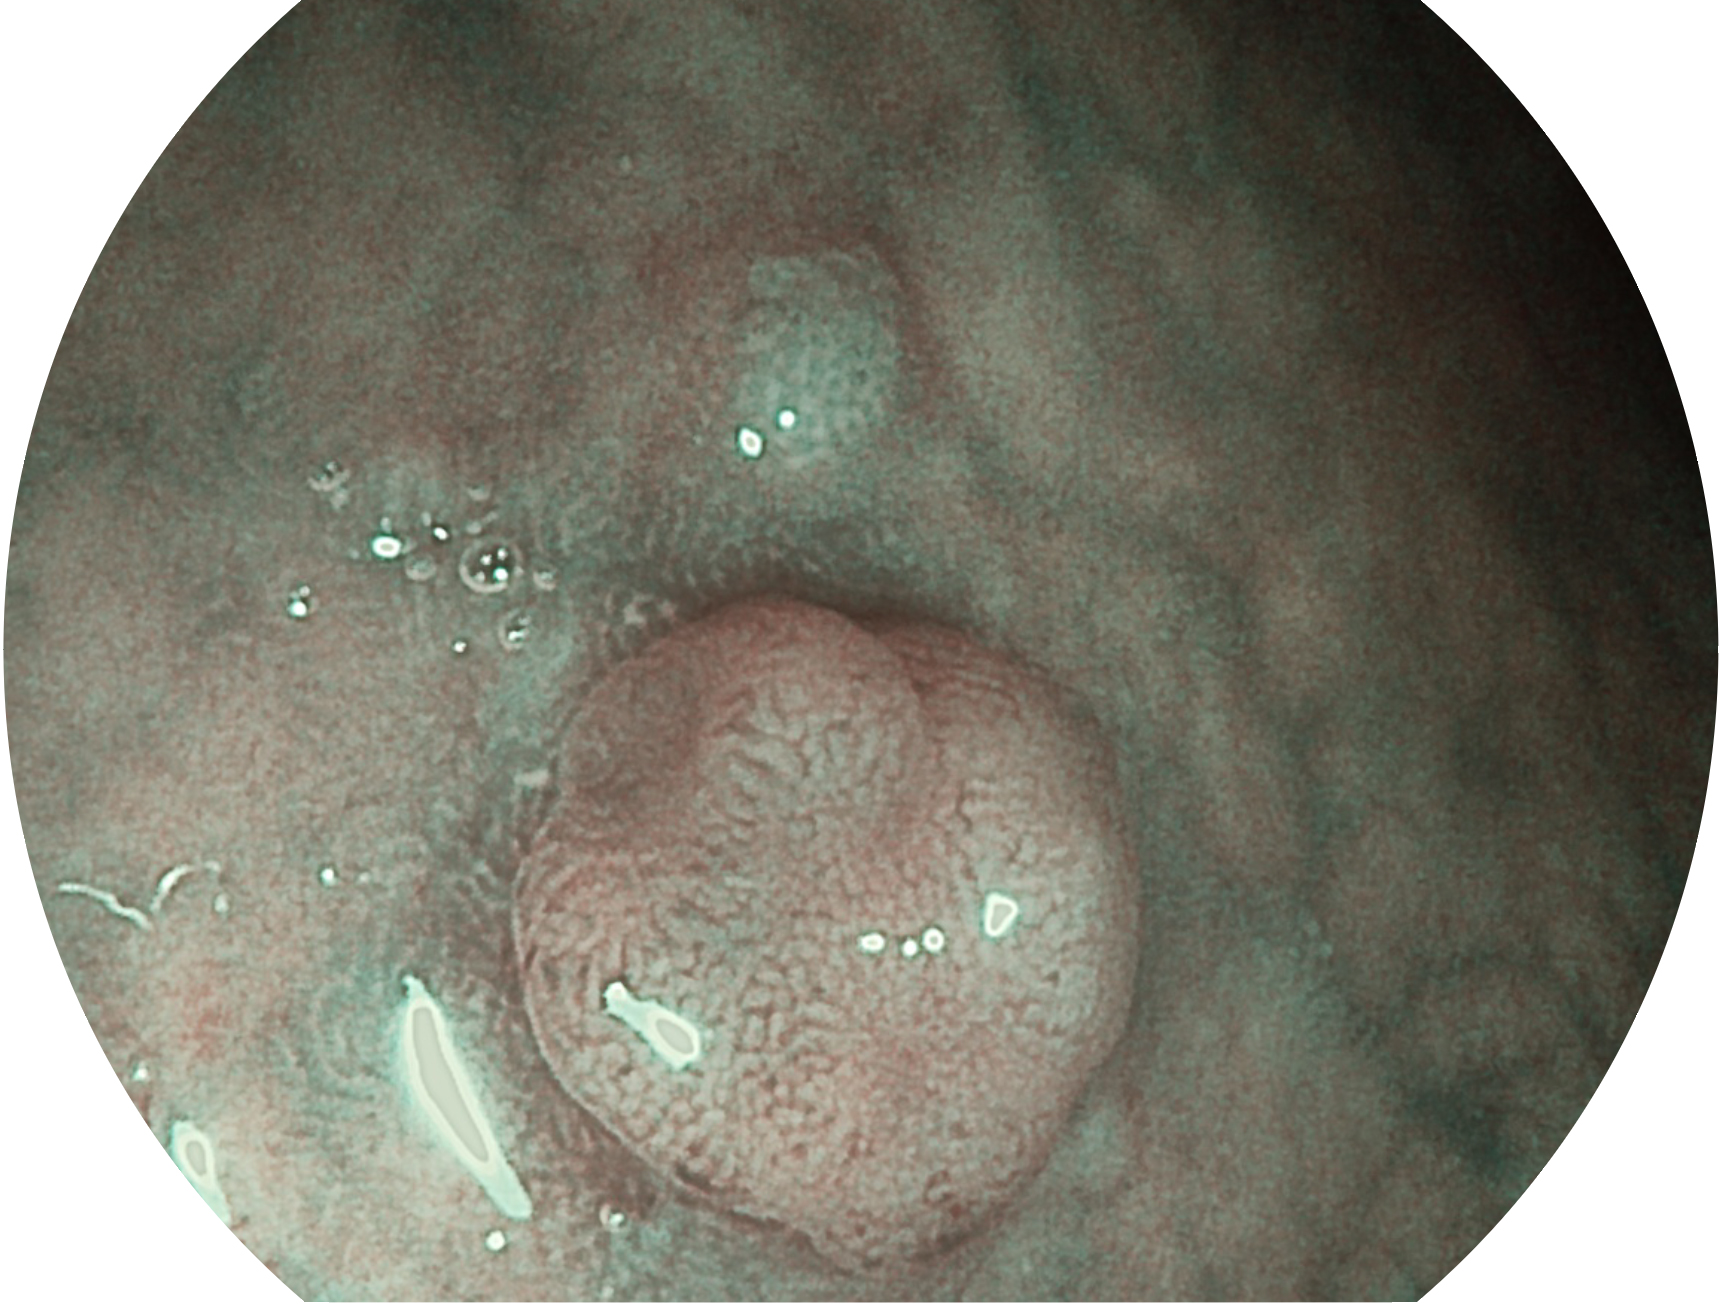

百老汇电子游戏官网新开发的内镜染色技术,主要是基于多波长LED 光源的开发,VLS-55Q 四波长LED 光源是由四个不同颜色的LED光按照相应照明模式所规定的特定发光比例进行合束后形成,合束后形成的照明光的光谱由红光、绿光、蓝光及蓝紫光这四个不同的波段范围构成。具有更高光谱自由度,通过光谱比例的控制,实现了聚谱成像技术,英文全称为“Spectral Focused Imaging, SFI”,缩写为“SFI”和光电复合染色成像技术,英文全称为“Versatile Intelligent Staining Technology, VIST”,缩写为“VIST”。